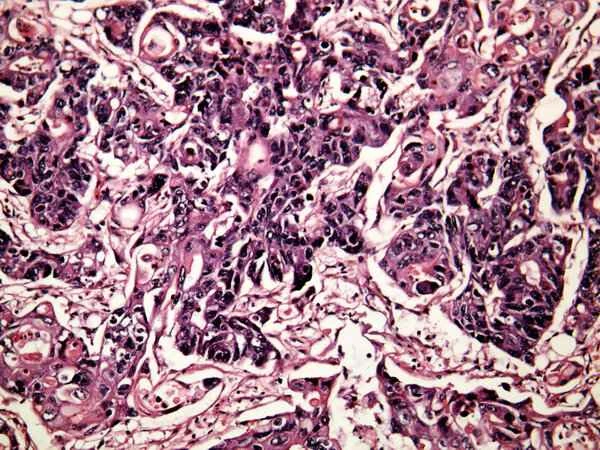

Tubular adenomas are a type of colonic polyp, usually discovered during colonoscopy. These polyps are formed by the abnormal proliferation of colonic mucosal cells, characterized by alterations in the glandular structure of the mucosal layer. While most tubular adenomas are benign, they have a certain potential to become cancerous, especially if left untreated. Once a tubular adenoma is discovered, endoscopic resection is usually necessary to prevent its potential malignancy. After resection, the doctor will determine whether further treatment or regular follow-up is needed based on the pathology results. The occurrence of tubular adenomas can be related to various factors such as genetics, diet, and lifestyle. Even after resection, lifestyle modifications are necessary to reduce the risk of recurrence.